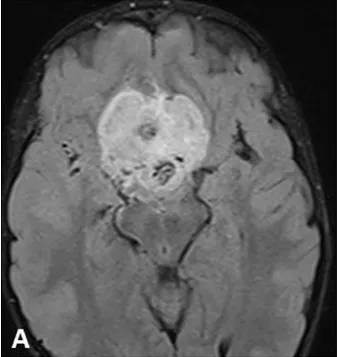

無論哪一型視神經(jīng)膠質(zhì)瘤,均由視力受損明顯側(cè)分塊切除腫瘤,保留視力、下丘腦及垂體柄功能是手術(shù)的較高原則。術(shù)后配合放療可以降低腫瘤復(fù)發(fā),提高患者的存活率。...